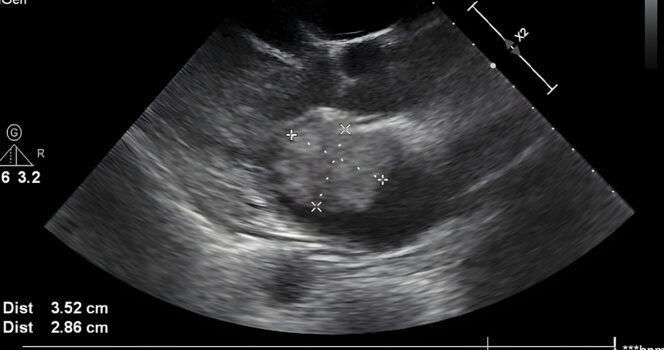

“I had an ultrasound yesterday, my youngest daughter Bailey was the first to notice it and asked me whose hand that was,” she writes in her now viral Facebook post. The post also includes a black and white image of the ultrasound, showing what she believes to be a divine presence of a giant hand cradling her son’s head. She adds: “In one of his pictures it has the appearance of a hand holding his head.”